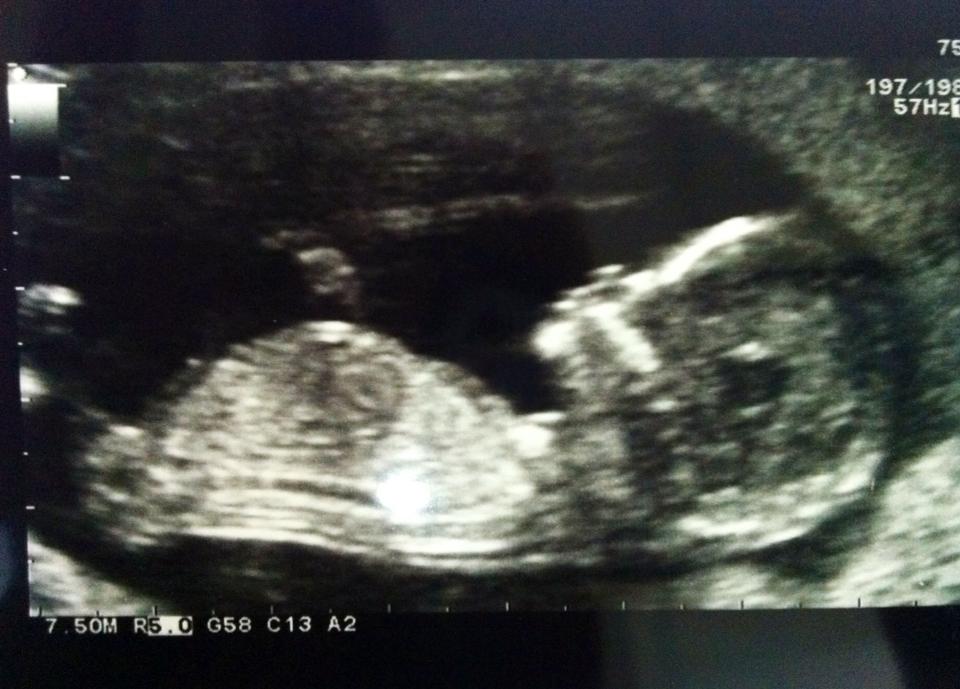

I'm a newbie and was wondering if anyone could kindly guess the gender of my baby - scan was at 13 weeks 1 day :)

Attachment 8201